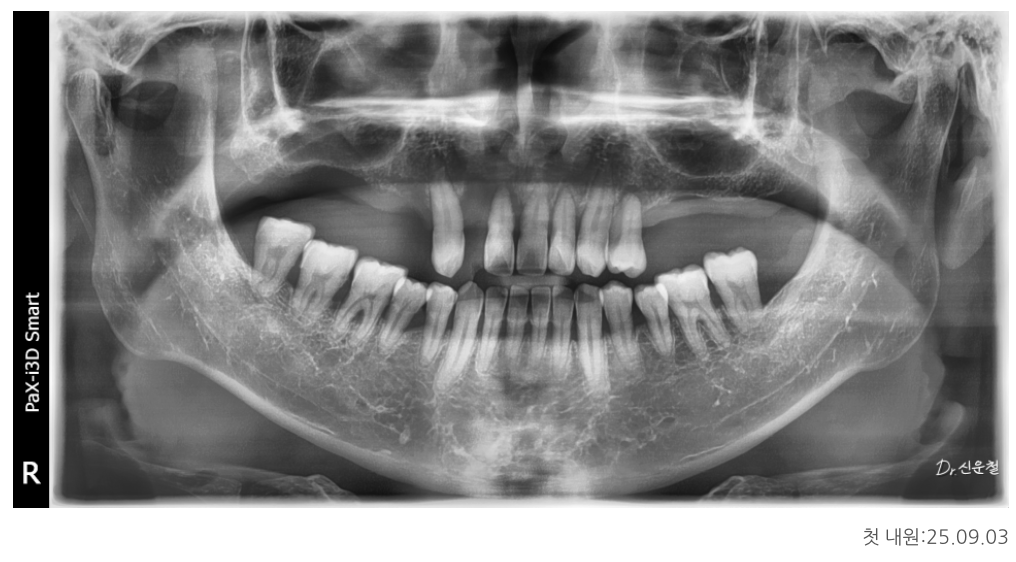

위턱·아래턱 상태 정밀 진단

위턱

남아 있는 치아 중 좌측 견치 1개만 보존 가능

견치는 뿌리가 길어 치조골 지지력이 비교적 좋은 치아

그 외 치아는 염증이 심하고 치조골 지지가 어려운 상태

아래턱

사랑니 발치 필요

양측 어금니는 신경치료 후 보철 치료가 불가피한 상태

앞니는 일부 남아 있었지만

오랜 염증으로 인해 치아를 지지하던 뼈가 많이 흡수된 상태였습니다.

상악동 거상술을 통한 기초 치료

위턱 어금니 부위는

오래전 치아를 상실해 임플란트를 바로 심기엔 뼈 높이가 부족했습니다.